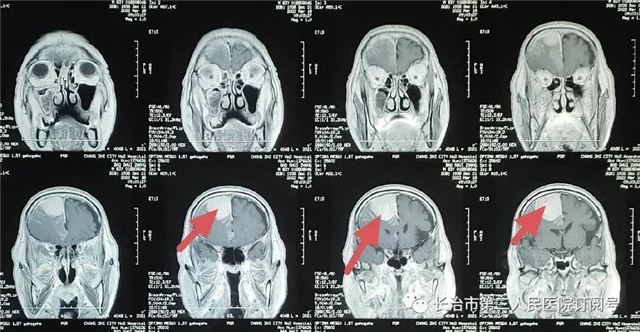

▲核磁检查见小脑幕下肿瘤,强化明显,考虑脑膜瘤。

(红色箭头为肿瘤)

▲术后复查:肿瘤全切、术野干净未见出血

本病例因幕下空间小,肿瘤压迫小脑,紧邻横窦、窦汇、脑干。手术风险高一旦出血,将危及生命。术后复查肿瘤切除干净,瘤腔未见出血。现患者已痊愈出院。